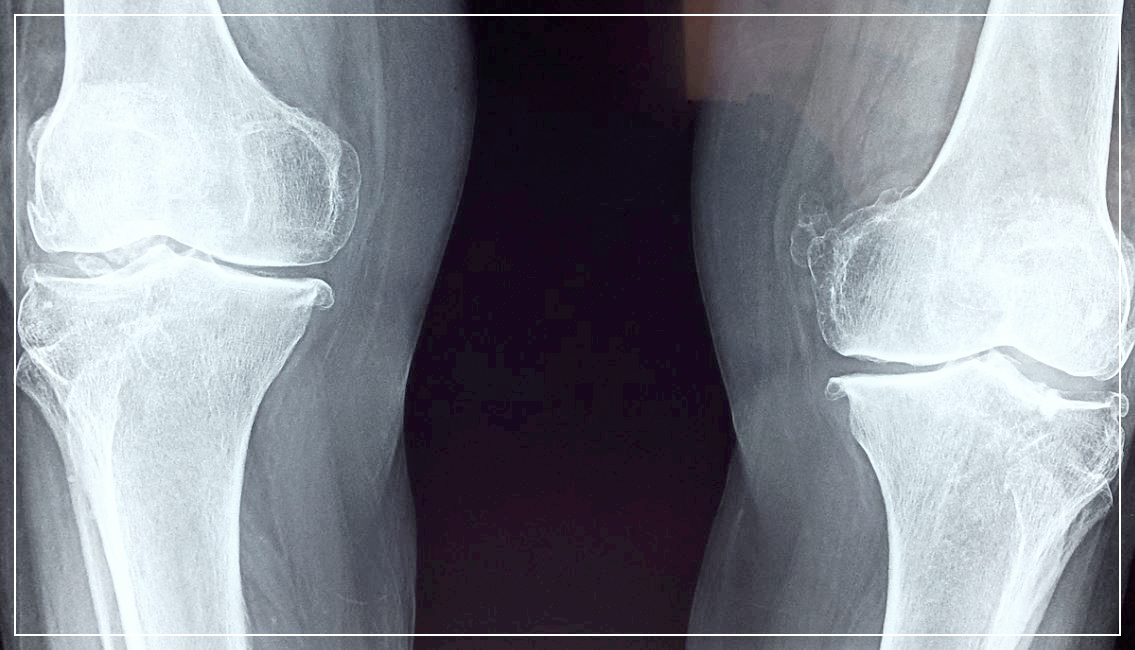

엠비피MBP는 골밀도를 증가시켜 골다공증 예방,

골강도를 증가 시키며

뼈형성지표를 증가,

뼈파괴지표인 NTx와 DPD감소 시킨다고 합니다.